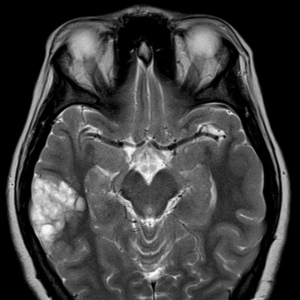

病例学习:神经上皮肿瘤

近期,AJNR杂志刊登了如下一则教学病例。上图为一个患颞叶癫痫男孩的头颅MRI,考虑诊断为?A. 神经节神经胶质瘤B. 神经上皮肿瘤C. 皮质发育不良D. 少突神经胶质瘤答案:B. 神经上皮肿瘤神经上皮肿瘤(DNETs)属良性肿 ...